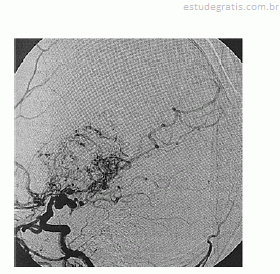

Paciente de 16 anos de idade, do sexo feminino, de asscendência japonesa, com deficits neurológicos progressivos iniciados ainda na infância, tem diagnóstico prévio de anemia falciforme. Realizou exame complementar de imagem do encéfalo, apresentado na reprodução acima. Há suspeita de doença de Moyamoya.

Em relação ao caso descrito, julgue os itens a seguir.

O aneurisma cerebral está associado à doença de Moyamoya.Comentários